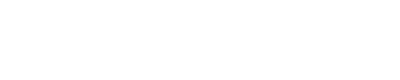

Yumurtalık zayıflığı, tıbbi adıyla primer over yetmezliği, yumurtalıkların yeterli düzeyde yumurta üretememesi ya da yumurtlama döngüsünü sağlıklı bir şekilde sürdürememesi durumudur. Bu durum, kadınların hormonal dengelerini de etkileyerek östrojen seviyelerinin düşmesine yol açabilir. Yumurtalık zayıflığı, menopozdan farklıdır çünkü bu durumdaki kadınlar hala düzensiz de olsa adet görebilir ve nadiren de olsa doğal yolla hamile kalabilir.

Yumurtalık Zayıflığı Tanısı Nasıl Konur?

Tanı koymak için genellikle birkaç farklı yöntem bir arada kullanılır:

| Test Türü | Açıklama |

|---|---|

| Hormon Testleri | Östrojen ve FSH seviyelerini ölçer. |

| Ultrasonografi | Yumurtalıkların büyüklüğünü ve folikül sayısını inceler. |

| Genetik Testler | Kromozomal anormallikleri belirlemek için kullanılır. |

| AMH Testi | Yumurtalık rezervini değerlendirmek için Anti-Müllerian Hormon testi yapılır. |